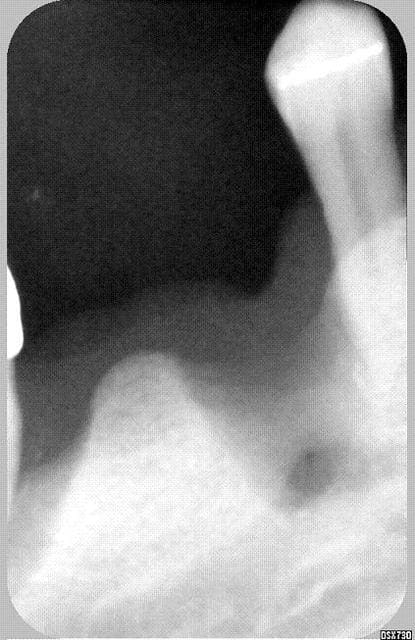

bon bin puisque personne ne donne d'exemple, je me lance.

c'est un cas que j'avais posté il y qq mois,et c'est le résultat (prévu par quelques uns...) aujoiurd'hui

Numériser isskw1 - Eugenol